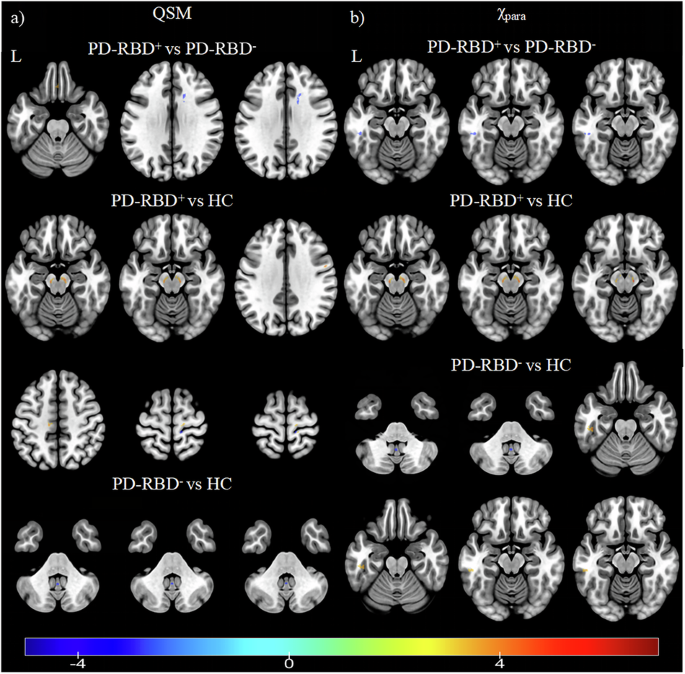

脑铁含量变化对PD继发RBD发展影响的具体机制尚不清楚。纳入继发性RBD患者27例(PD-RBD+),无RBD患者24例(PD-RBD-),健康对照32例(hc)。采用APART-QSM分离顺磁化率。比较各组全脑和皮质下核的QSM和顺磁化率(χpara)值。采用受试者工作特征曲线分析对诊断性能进行评价。与PD-RBD-相比,PD-RBD+患者左侧颞中回的χpara值较低。两组患者双侧黑质致密部(SNpc)的QSM和χ 2值均升高。χpara值联合指标的诊断效能优于QSM值或单一指标。综上所述,从QSM中分离出的顺磁化率有助于铁的定量和探索PD-RBD+的机制。

The specific mechanism underlying the effect of changes in brain iron content on the development of RBD secondary to PD remains unclear. 27 PD patients with secondary RBD (PD-RBD+), 24 PD patients without RBD (PD-RBD-), and 32 healthy controls (HCs) were included. Paramagnetic susceptibility was isolated using APART-QSM. The QSM and paramagnetic susceptibility (χpara) values of the whole brain and subcortical nuclei were compared among groups. The diagnostic performance was evaluated using receiver operating characteristic curve analysis. Compared with PD-RBD-, PD-RBD+ patients presented a lower χpara value in the left middle temporal gyrus. The QSM and χpara values of bilateral substantia nigra pars compacta (SNpc) were increased in both groups. The diagnostic performance of the combined index of χpara values was superior to that of the QSM value or the single index. In conclusion, paramagnetic susceptibility isolated from QSM is helpful for iron quantification and exploring the mechanism of PD-RBD+.